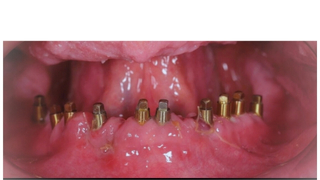

ВСТАНОВЛЕННЯ ІМПЛАНТУ

Абсолютно безболісно встановлюються імплантати у правильну позицію завдяки сучасним апаратам сканування 3Д діагностики. При необхідності додатково проводяться процедури з нарощування кістки та робота зі слизовою оболонкою навколо імплантатів.